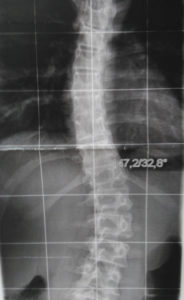

Durch jahrzehntelanger Erfahrung in der Behandlung von Wirbelsäulen können wir die Herstellung von fixierenden und stabilisierenden sowie wachstumslenkenden Rumpforthesen nach modernsten Kriterien gewährleisten.

Rumpforthesen werden eingesetzt, um die Wirbelsäule zu fixieren, zu korrigieren (Redression), aufzurichten (Reklination), zu entdrehen (Derotation) oder zu strecken (Extension). Unterschieden werden passive und aktive Rumpforthesen. Die passiven Rumpforthesen, auch Stützkorsetts genannt, werden zur Entlastung instabiler Wirbelsäulen eingesetzt, u.a. mit dem Ziel der Schmerzlinderung. Aktive Rumpforthesen sollen Fehlstellungen der Wirbelsäule korrigieren, wie sie bspw. als Folge von Erkrankungen wie Skoliose, Kyphose, Morbus Scheuermann, Hyperlordose und Osteoporose auftreten. Rumpforthesen werden bei Kindern und Jugendlichen eingesetzt, um das Wachstum zu lenken und Fehlstellungen zu korrigieren.